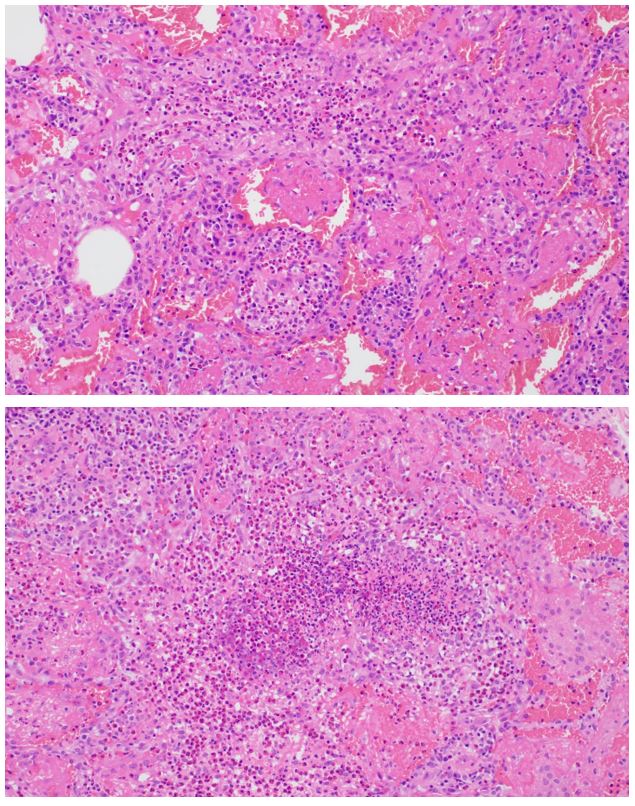

Video-assisted thorascopic surgery wedge biopsy of the right lower lobe: – H&E sections (3):